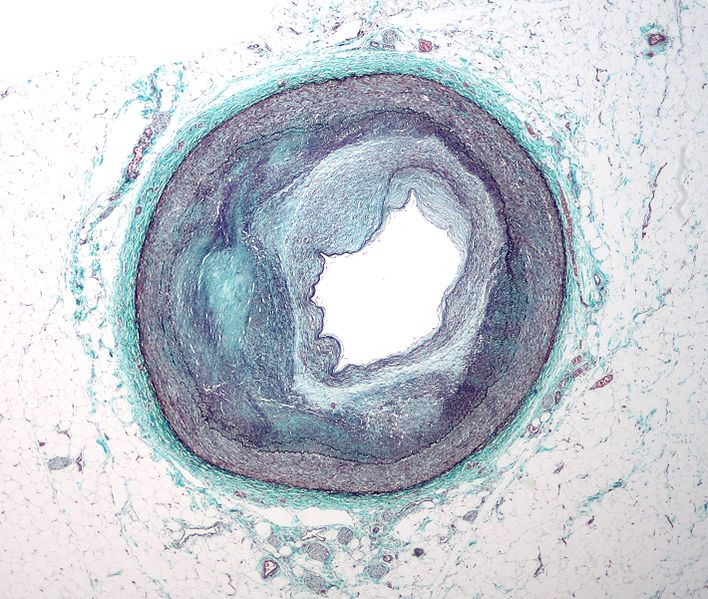

An important new acupuncture study from the Department of Nuclear Medicine at Peking University Shenzhen Hospital successfully measured improvements in blood flow to the heart for patients with coronary heart disease (CHD). Using single photon emission computed tomography (SPECT), researchers discovered that needling two specific acupuncture points caused significant improvements in patients with CHD. Acupuncture successfully increased “blood perfusion of ischemic myocardium.”

Blausen_0257_CoronaryArtery_PlaqueCoronary heart disease is due to plaque build-up in the walls of the coronary arteries, a condition known as atherosclerosis. This build-up can narrow the coronary arteries and lead to a decrease of oxygen rich blood flow to the heart. Myocardial ischemia, a condition wherein blood flow to the heart is decreased due to a blockage of the coronary arteries, can cause damage to the heart, arrhythmias, angina or even a heart attack. Conventional treatments to improve blood flow to the heart muscle include medications and surgical procedures. The new findings demonstrate that acupuncture has the ability to improve blood flow to the heart.

The study included a total of 59 patients with CHD. They were randomly assigned to 2 groups. Group 1 consisted of 32 patients and group 2 consisted of 27 cases. Group 1 received acupuncture and group 2 received nitroglycerine, a substance used in the treatment of angina, chronic heart failure, heart attacks and other heart conditions. Nitroglycerine converts to nitric oxide, a potent vasodilator. It widens the blood vessels and improves blood flow to the heart.

Given the heart related historical use of the acupuncture points tested, the point selection is congruous with the focus of the study. The researchers concluded that both acupuncture and nitroglycerine increased blood perfusion to ischemic myocardium in patients with coronary heart disease. As a result, the researchers noted that acupuncture SPECT technology “clearly display(s)” the “therapeutic effects of acupuncture on CHD, thus providing a new visible research method for CHD studies.”